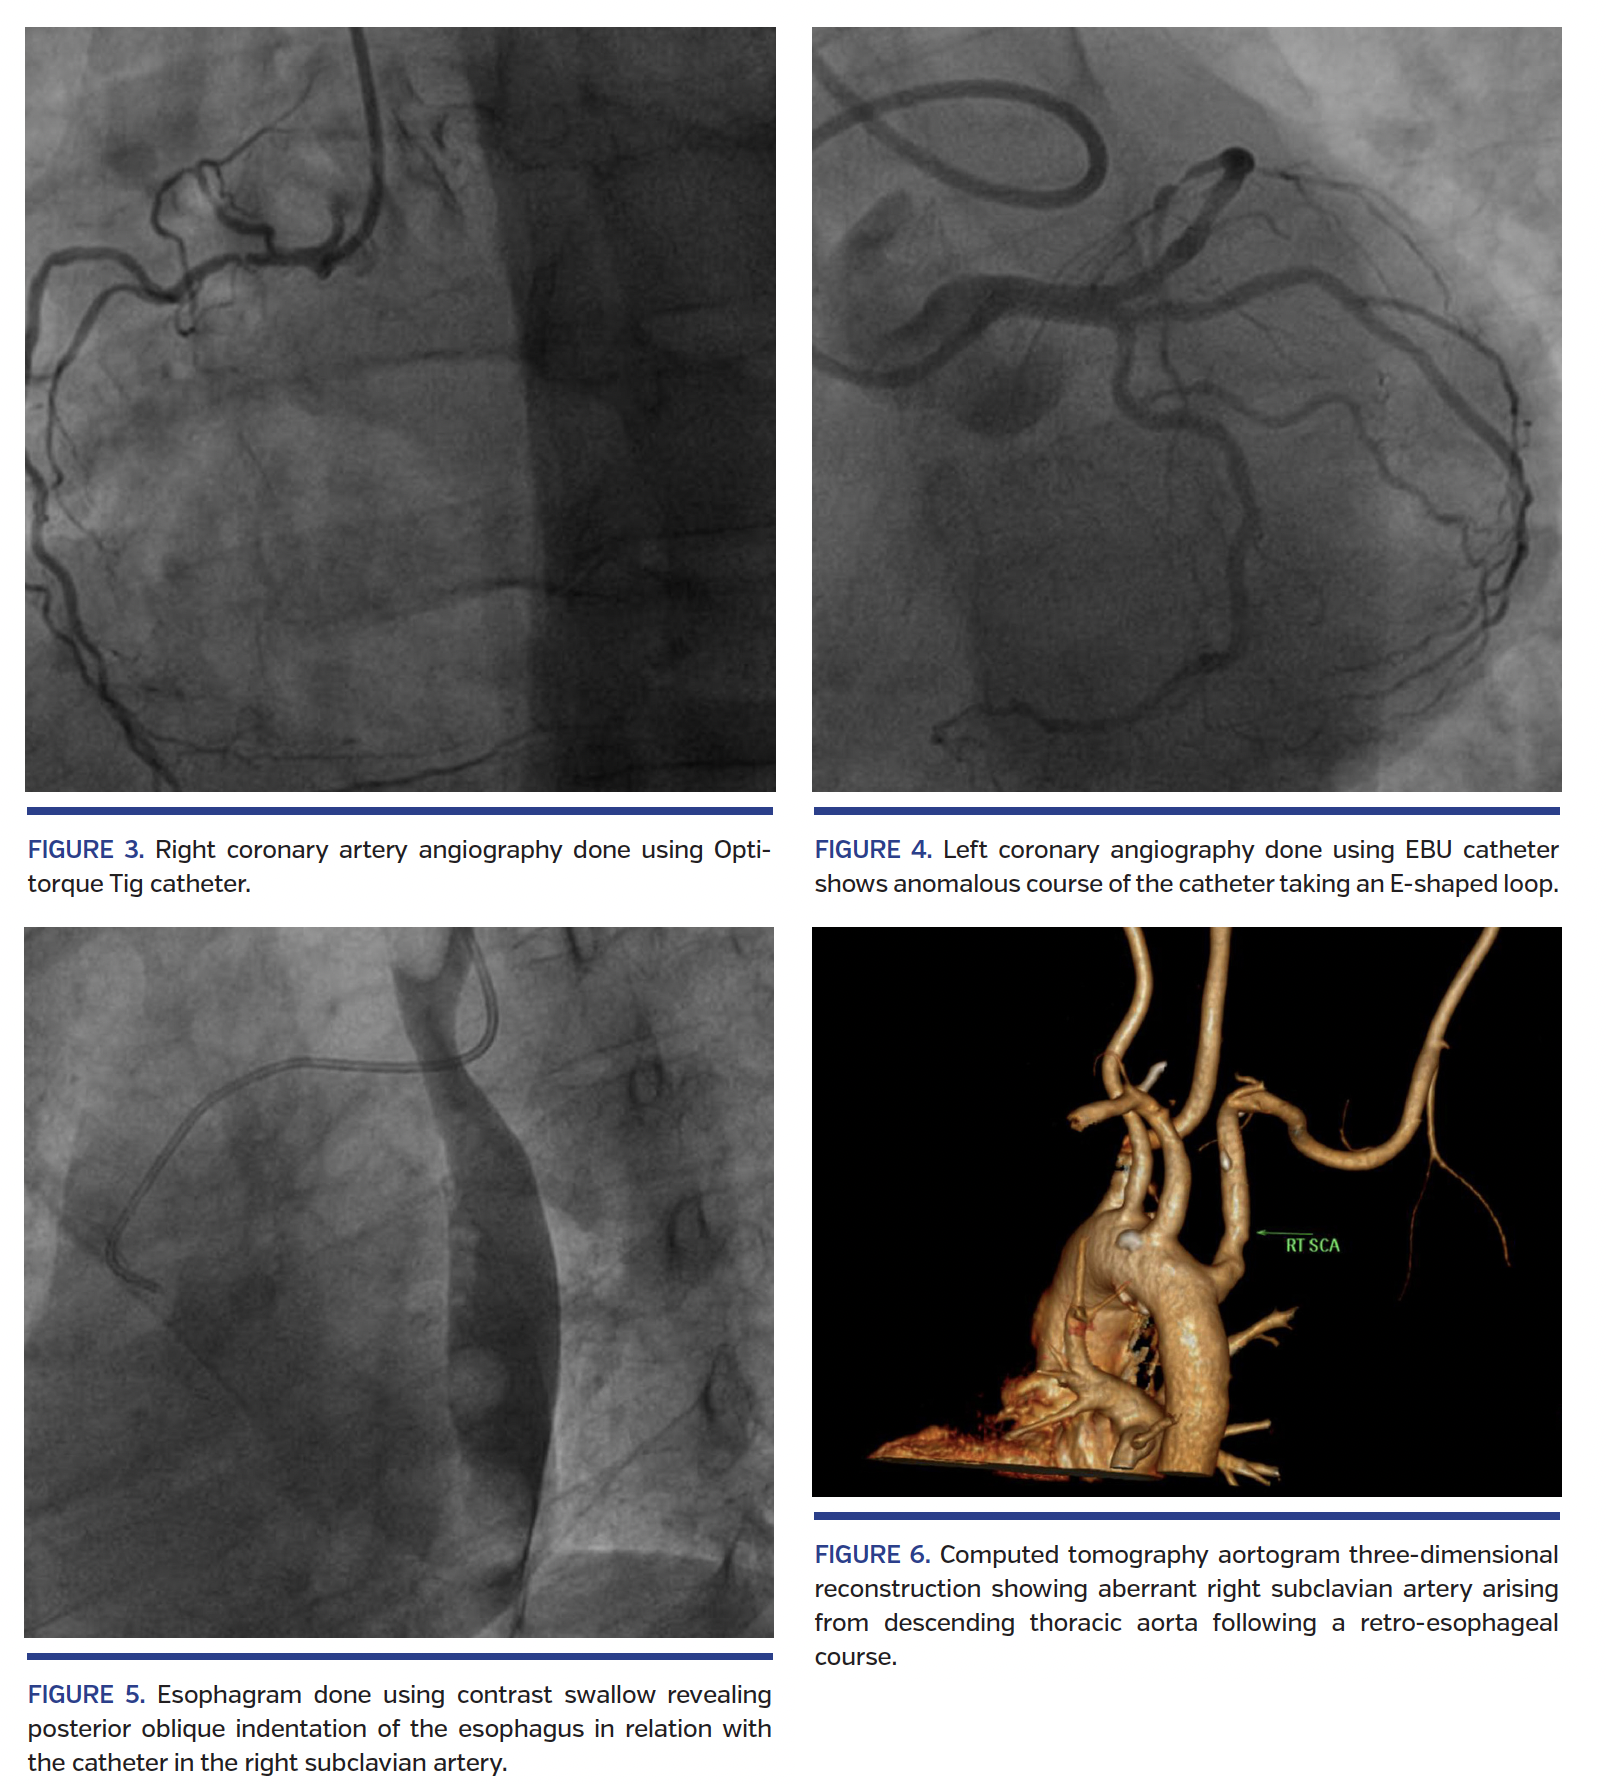

A 56-year-old male diabetic was admitted with diagnosis of evolved anterior-wall myocardial infarction (MI) with post-infarct angina. The results of a physical examination were unremarkable. Electrocardiogram showed features of evolved anterior-wall MI and cardiac biomarkers were elevated. Echocardiography showed hypokinesia in the left anterior descending (LAD) territory; left ventricular ejection fraction was 45%. Coronary angiography via right radial artery was planned. During coronary angiography, a 0.035˝ guidewire (Terumo) repeatedly entered the descending thoracic aorta. Contrast injection in the abnormal artery showed right subclavian artery arising from descending thoracic aorta (Figure 1; Video 1). However, with the tip of the Optitorque Tig catheter (Terumo) directed toward the aortic arch, the guidewire could enter the arch and ascending aorta (Figure 2; Video 2). The right coronary artery was cannulated with the Optitorque catheter with difficulty (Figure 3; Video 3), but it was not possible to cannulate the left coronary artery with the same catheter. The Optitorque catheter was exchanged to a 3.5 Extra Backup 6 Fr guide catheter and the left coronary artery was engaged cautiously with the help of the reverse end of a 0.035˝ guidewire taking a E-shaped loop (Figure 4; Videos 4A and 4B). The right coronary artery was normal and the mid LAD showed focal critical stenosis. The LAD was stented with a 2.5 x 18 mm drug-eluting stent. Later, esophagogram with contrast swallow revealed posterior oblique indentation of the proximal esophagus in relation with the catheter in the right subclavian artery (Figure 5; Video 5). Subsequently, computed tomography aortogram confirmed the aberrant right subclavian artery arising from the descending thoracic aorta following a retroesophageal course, resulting in a prominent compression of the esophagus, a finding consistent with arteria lusoria (Figure 6). Most patients with an aberrant subclavian artery are asymptomatic, and with the increasing popularity of transradial access to perform coronary angiography, arteria lusoria may be discovered as an incidental surprise. Transradial coronary angiography and interventions in patients with arteria lusoria, while technically challenging, are feasible without crossover to femoral approach. Interventional cardiologists should be aware of this rare entity when guidewire or catheter repeatedly enter the descending thoracic aorta rather than the ascending aorta during transradial coronary intervention.